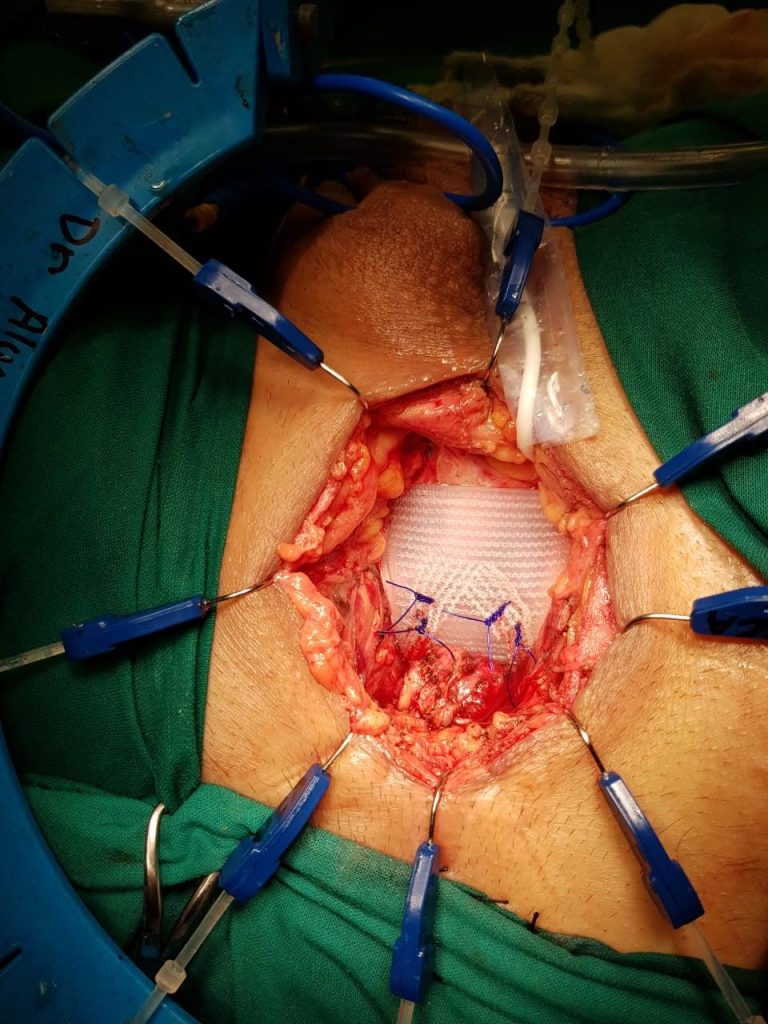

La técnica transvesical (de O’Connor) se basa en una cistotomía amplia desde el domo vesical hasta llegar a la fistula por posterior, con adecuada visualización y eventual cateterización de los uréteres (Figura 25). Se debe realizar una cuidadosa disección del plano vesicovaginal (Figura 26). Cierre de la pared vaginal con material reabsorbible 3-0 y luego cierre de la vejiga con similar sutura (Figura 27). Se puede además movilizar un colgajo de peritoneo o epiplón que se interpone entre ambas suturas.